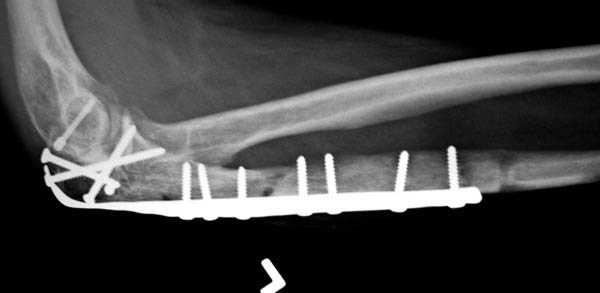

Снимки вот еще какие есть (наши лаборанты пытались сделать что то)

|

Как минимум два фрагмента, включающих суставную поверхность, и много (т.е. более двух) околосуставных осколков метафиза

О Вебере в данном случае не может быть и речи , поскольку фиксация стягиванием предполагает наличие опоры на неповреждённую косточку , чего тут нет совсем ! только пластинка , и очень хотелось бы посмотреть снимки после операции , даже если получится и не очень хорошо . Очень уж сложный перелом .

Для фиксации перелома локтевого отростка на сегодня множество преконтурных с блокирующими возможностями пластин.

Стабильную фиксацию, особенно при оскольчатых

переломах, можно добиться, применяя технику Bridge Plate, и за счет тех пластин, где имеется возможность проведения множественных шурупов (2.7 мм) проксимально.